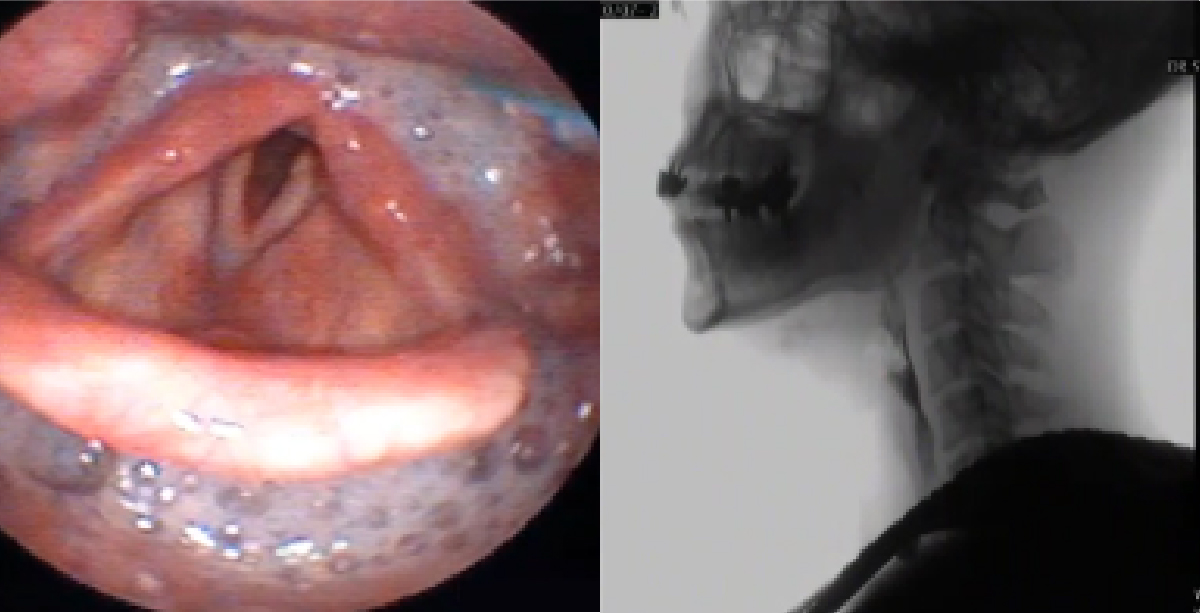

嚥下内視鏡検査、嚥下造影検査の実施

食べ物や飲み物を食べること、飲み込むことに支障をきたしている方に嚥下内視鏡検査(VE)と嚥下造影検査(VF)を実施しています。